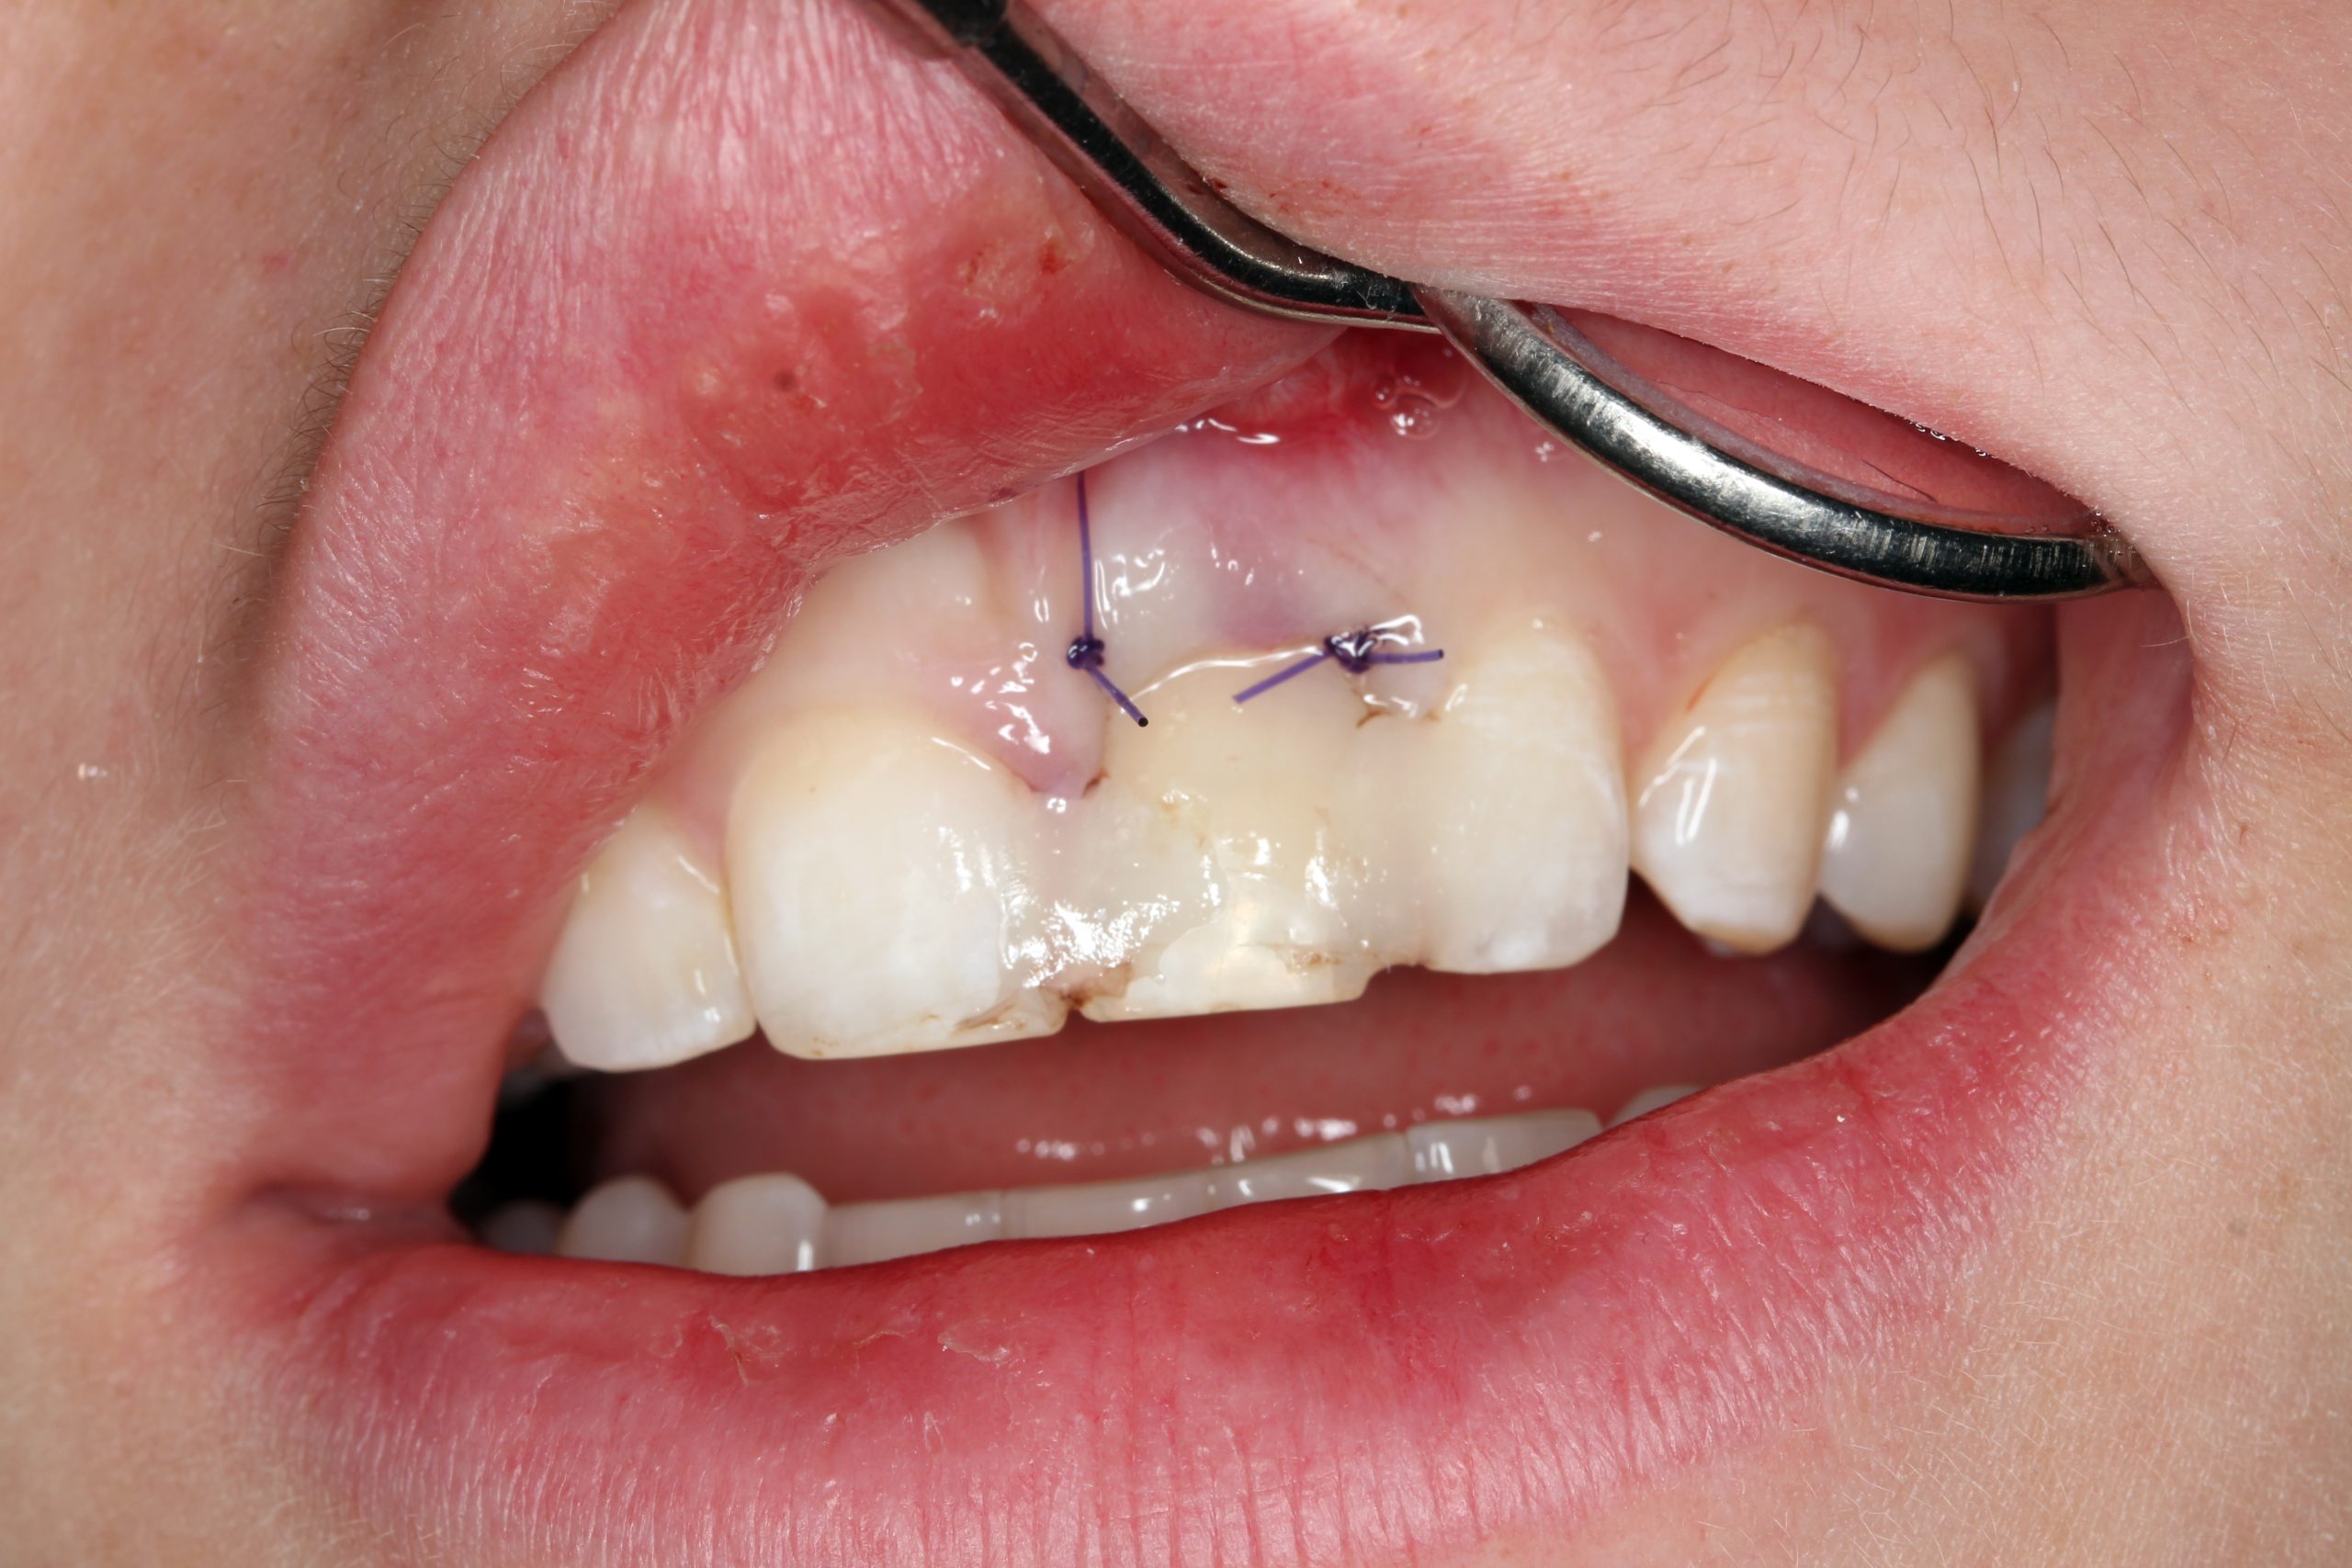

After extraction and excochleation, the extraction wound was revised. The vestibular wall of the socket was preserved except for the apical part. The tooth bed was only filled with an antibiotic-containing collagen cone.

The extracted tooth was used as a temporary restoration. The root was cut approximately 2 mm below the CEJ so that this part was embedded in the soft tissue. The crown was cemented to the adjacent teeth with composite.